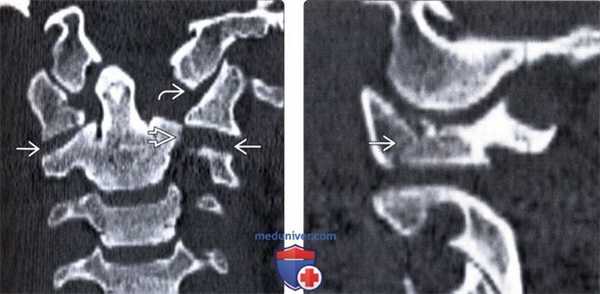

(Справа) На сагиттальном КТ-срезе у пациента с АЗД определяется увеличение расстояния между базионом и верхушкой зуба (желтая линия), патологическое увеличение расстояния между базионом и задней аксиальной линией (оранжевая линия). Задняя аксиальная референсная линия обозначена белым. (Слева) На парасагиттальном КТ-срезе у пациента с АЗД определяется расширение суставных щелей сочленений С0-С1 и С1-C2. Суммарное смещение мыщелков (сумма расстояний между центральными точками мыщелков затылочной кости и суставных впадин С1 с обеих сторон) считается патологическим, если оно превышает 4,2 мм.

(Справа) На сагиттальном STIR МР-И определяется патологическое расширение и усиление сигнала суставных щелей сочленений С0-С1 и С1-С2. Этому пациенту по поводу атланто-затылочной и атланто-аксиальной диссоциации был выполнен задний спондилодез протяженностью от затылочной кости до СЗ позвонка. (Слева) КТ, аксиальной срез: множественные переломы кольца С1 без признаков компрессии спинномозгового канала.

(Справа) КТ, аксиальной срез: переломы передней и задней дуг С1 в сочетании с отрывом костного фрагмента на уровне прикрепления поперечной связки атланта.